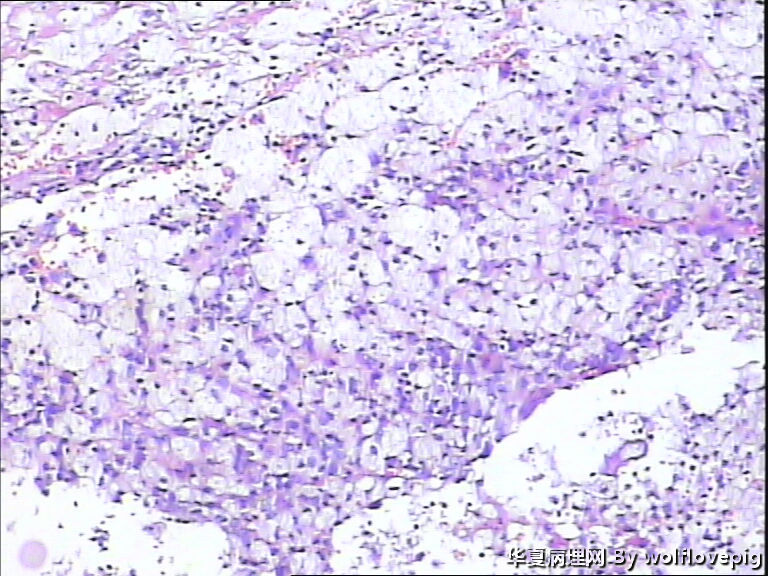

31y,阴蒂附近囊肿2.0*1.5cm

外阴最常见的囊肿是前庭大腺囊肿,囊肿一般衬以移行上皮,常伴有非角化性鳞状化生,也有的呈扁平或立方状,囊肿周边附近可以见到黏液腺体。

此例有点特殊,看到一些纤毛柱状上皮被覆,称为纤毛囊肿,属于前庭大腺囊肿的特殊改变。

前庭大腺囊肿位于外阴后半部,而此例位于阴蒂附近。

泌尿生殖窦起源的外阴囊肿(粘液性和纤毛囊肿)

1,多见于21-30及31-40的多产妇女,病变多位于外阴前庭。

2,组织学上,粘液性囊肿含有与宫颈内膜或阴道腺病一样的粘液性上皮内衬,少数情况下可出现鳞状上皮化生。也有报道有些病例出现纤毛细胞,可以与粘液上皮混合存在。